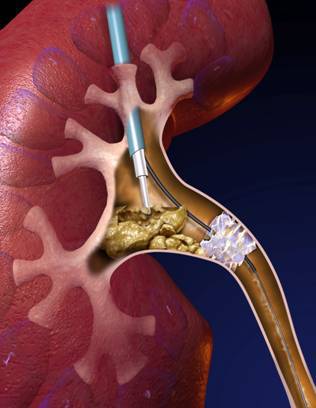

经皮肾镜碎石取石术(PCNL):是指通过腰部皮肤到肾脏之间制作一微小通道,通过此通道将纤细的内窥镜伸入到肾脏的结石部位,利用腔内碎石、取石器械,将结石击碎、取出的微创技术。也就是首先在患者腰背部打一个约筷子粗细的洞,建立一个隧道并看到“可恶”的石头之后,再利用我们的内窥镜以及碎石设备(比如传说中高大上的激光、超声、气压弹道等),像武侠小说中的六脉神剑一般,很快地结石粉碎掉,然后将结石从该隧道冲洗出体外,最后放置肾造瘘管以及输尿管支架管引流,完成整个手术过程。

相较于传统手术刀口要像蜈蚣一般长达20厘米,且依靠医生手指伸进病人肾脏内掏石头,对于复杂结石,在肾脏内分支很多,开刀手术要想取干净这些多分支的结石是很难的,就算取了大部分结石,也是将肾脏剖开,取出结石后,再将肾脏钉合缝合起来,牺牲了大量的肾脏正常组织功能,结石虽然取出来了,肾功能也丢失了不少,容易造成“同归于尽”的结局,很多病人早年经历开放肾切开取石后出现肾萎缩的结果。而经皮肾镜刀口只有普通筷子直径那么大,所以该技术具有创伤面小,恢复快的优点。而且通过内窥镜的探查,可以发现的结石的各个分支,我们可以很直观的看到结石并粉碎,而不是靠飘忽的经验、手感去掏,所以取干净结石的几率也是大大增高,同时最大限度的保留了肾功能,因而随着这一技术的诞生和发展成熟,目前已经取代传统的开刀手术成为了复杂肾结石治疗的“金标准”。

3、碎石取石

直捣肾脏之后,置入内窥镜,利用持续的水流的冲开最后一道防线,杀向我们的敌人——结石。神兵天降,让*弹子**飞一会儿吧!结石到了最危险的时候!这时我们的终极*器武**,气压弹道、钬激光或者超声这三大秘密*器武**就粉墨登场了!“气压弹道”就好比机关机枪,突突突突将结石打个片甲不留,如降龙十八掌般气势如虹;“钬激光”就像把镭射枪,如同六脉神剑般悄然间把结石消融掉;而“超声碎石”则是把超声波枪,不知不觉让结石粉身碎骨并直接吸出肾脏外,好比化骨绵掌。碎石过程中,整个手术室就像维也纳金色大厅,响起了一首首欢快的碎石乐章!